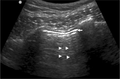

Abnormal